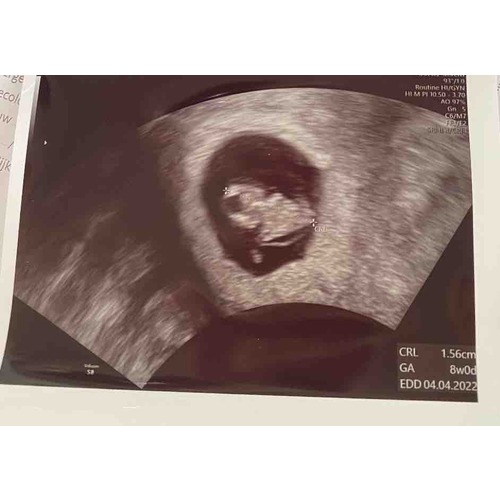

Mijn echo van afgelopen maandag bij 7+4. Helemaal onderin gelegen met het hoofdje rechts, twee ‘stompjes’ die uit moeten groeien tot armpjes. Daarboven het vruchtzakje. Zo bijzonder hoe ze dat allemaal al kunnen zien! Ik ben benieuwd naar de volgende echo.